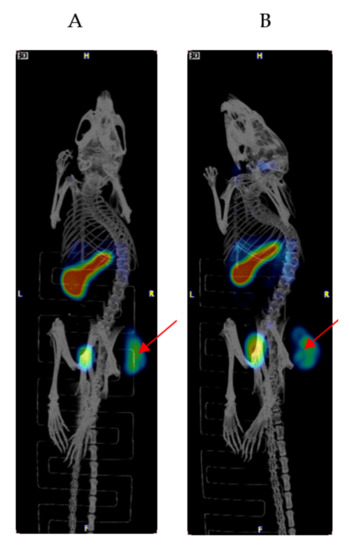

2.1. Biodistribution and Microspect/CT Imaging Demonstrated a High Uptake of the IF3 Antibody in Canine-Patient-Derived Gracie Tumors